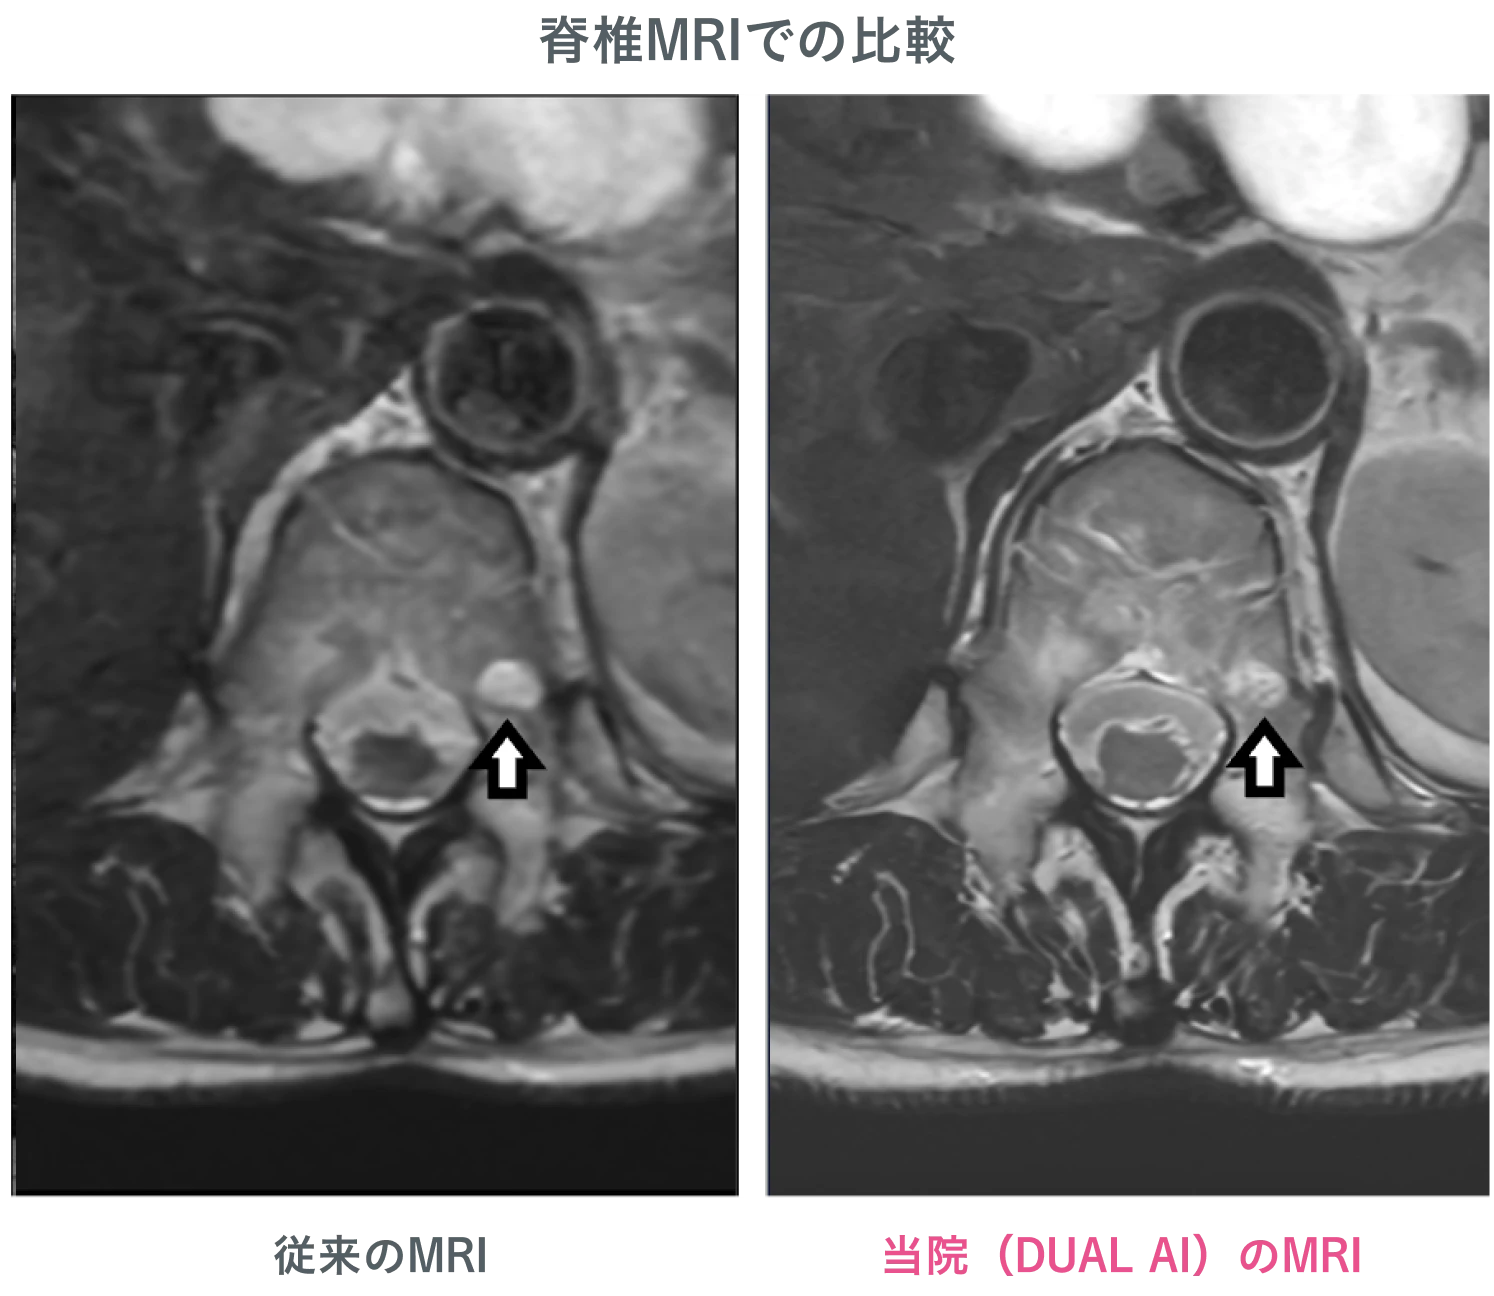

AI を搭載した最新鋭MRI・CTを導入

医療技術の進化を取り入れ、高精度な検査を実現。AI による画像解析により、見落としのリスクを最小限に抑えます。